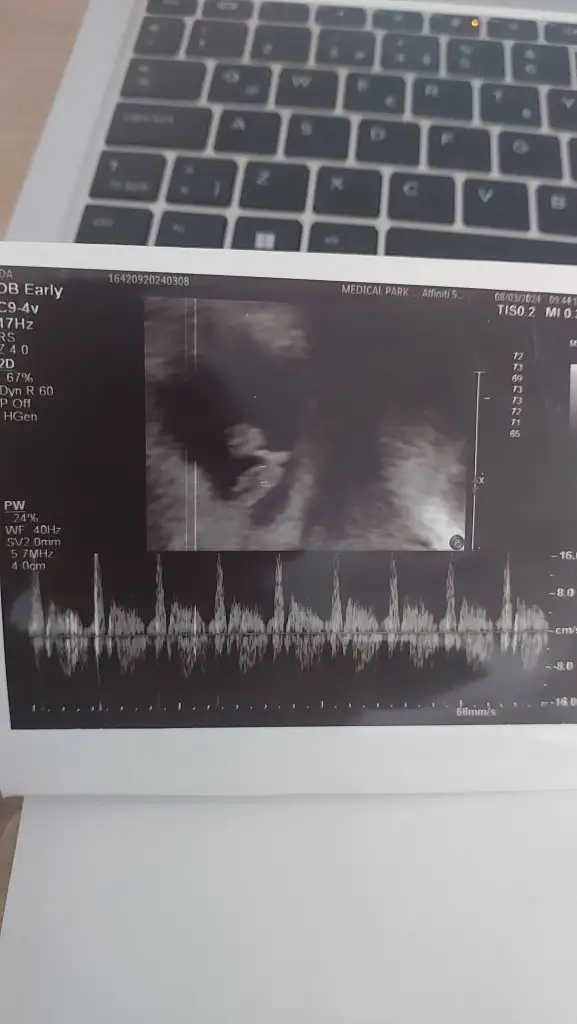

Bu arada beta hcg çıkmış kızlaer

5+0

3663 çıkmış

Ve doktor bu değerle göremedi bebeği.

Yaaa baska hastahanede gordun mu cok sevindim alttan bakinca cok rahat gorur yaa bende sasirdim degerin az degilGöremezler canım ultrason kalitesinden dolayı3124 çıktı doktor bakıyor kese falan yok dedi. Çıktım hemen başka hastaneye gittim. Bakar bakmaz gördü doktor keseyi. Kusura bakma da neresiyle bakmış dedi doktor